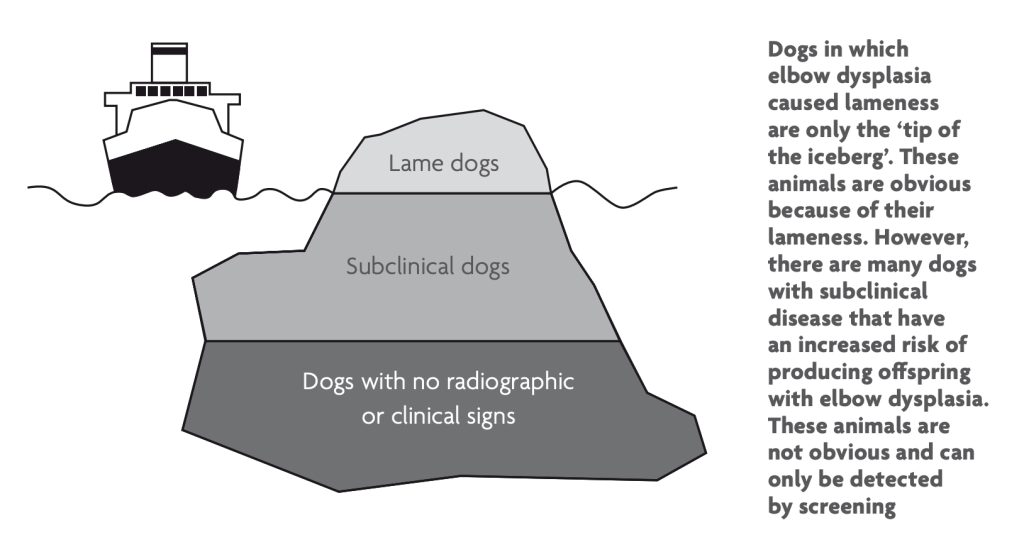

ED (Elleboogdysplasie)

Wat is elleboog dysplasie?

Elleboogdysplasie (ED) is een erfelijke aandoening waarbij het ellebooggewricht zich abnormaal ontwikkelt. Dit kan leiden tot pijn, kreupelheid en uiteindelijk artrose. Het is een multifactoriële erfelijke aandoening, waarbij omgevingsfactoren ook een rol spelen tijdens de ontwikkeling. Sommige honden kunnen op jonge leeftijd al ernstige problemen ondervinden door ED. Bij andere honden leiden ernstige misvormingen in het gewricht pas op latere leeftijd tot kreupelheid. Symptomen van ED kunnen zijn:

Hoe wordt heupdysplasie gediagnosticeerd?

Om te kunnen meten of een hond ED heeft, zijn röntgenfoto’s van zijn gewrichten nodig, dit is mogelijk vanaf een leeftijd van 18 maanden. Het aantal te maken röntgenfoto’s verschilt per ras, bij de aussies worden er vier foto’s gemaakt. Het ED-onderzoek richt zich op eventuele artrose en de volgende vier verschillende aandoeningen van het ellebooggewricht, LPCM, LPA, OCD en incongruentie. Al deze aandoeningen kunnen leiden tot misvormingen in het gewricht en kreupelheid.

Uit een ED onderzoek kunnen de volgende uitslagen komen, gebaseerd op de FCI normen:

- Vrij

- Graad 1

- Graad 2

- Graad 3

Wat betekent dit tijdens het fokken?

Tijdens de fok worden alleen honden ingezet met de uitslag “vrij”, “free” of “normal”. Honden met een graad 1, 2 of 3 worden bij de Australian Shepherd altijd uitgesloten van de fok.

(The British Veterinary Association and The Kennel Club & Jones, 2022.)